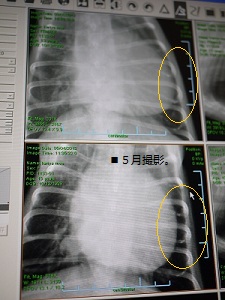

今日は久しぶりにレントゲンを撮りました。

5月にガァ子ちゃんの咳が出た時以来。

下が5月の画像で、上が今日。

黄色い○で囲った部分。

隙間が無くなってるのが分かりますよねぇ・・。

心臓の肥大が進んでる証拠です(T▽T;)